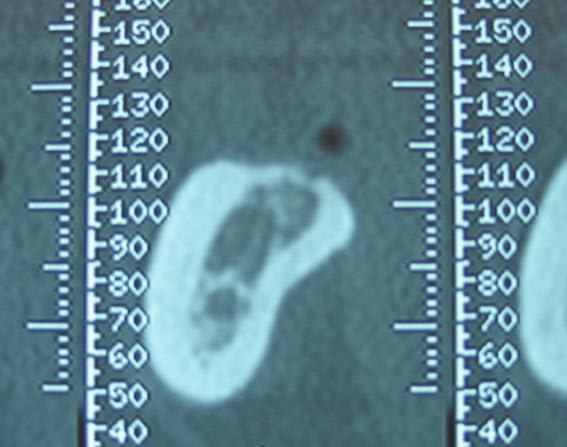

tu exagere ivétol : tu mesure 11,2 mm, et tu simule un implant de 11 : normal d'être dedant.

Si il y a 11,2 mm de mesuré, que tu enleve une imprecision de 1 mm, et les 2 mm de sécurité requis au dessus de nerf mand, tu arrive à ton choix d'un implant de 8 mm !

ta corticale interne ne va pas se laisser forer comme tu le proposes sur ton scanner...

il faut disposer de plus de coupes et je te conseille l'usage d'un logiciel adapté à l'examen des scanners en 3D...